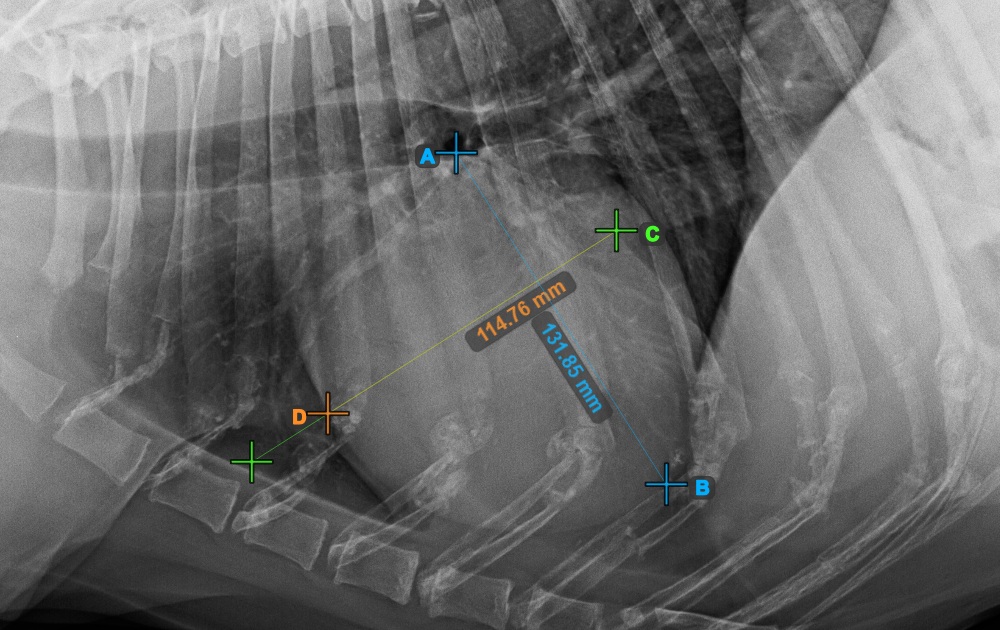

Complete the short axis of the heart by marking the widest left (caudal) point.

The image below represents the typical placement of the most caudal point on the short axis of the heart.